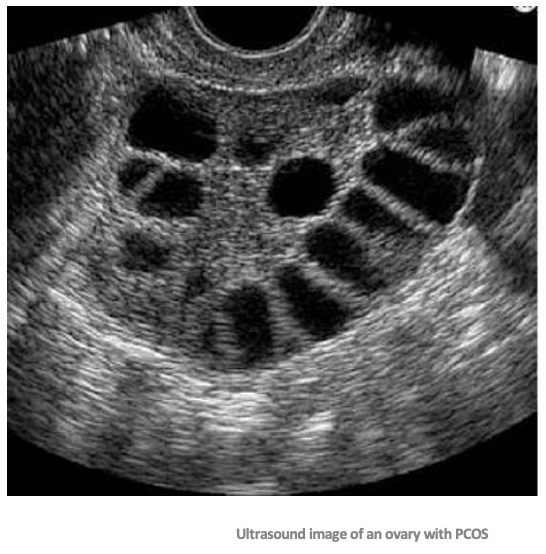

What is the difference between a normal ovary and a PCOS ovary on ultrasound?

Diagnostics: Ovarian Types

Normal ovary:

Multiple follicles develop

One becomes dominant → ovulation (egg released)

Others regress and are reabsorbed

PCOS ovary:

Follicles begin to grow but get arrested (don’t fully mature)

No dominant follicle → no ovulation

Follicles do not regress → accumulate in ovary